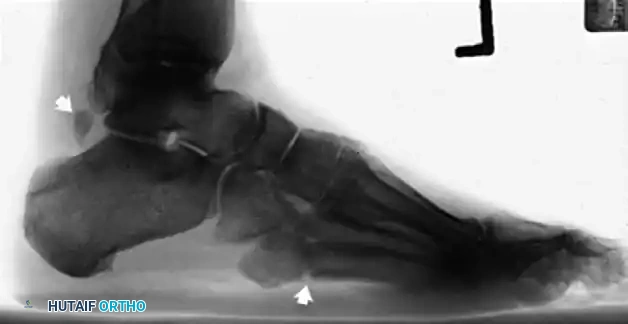

- Plain Radiographs: Weight-bearing anteroposterior, lateral, and mortise views of the ankle and foot are obtained to rule out fractures (e.g., "fleck sign" indicating SPR avulsion), os peroneum pathology, or varus hindfoot alignment.

Lateral radiographic view of the ankle.